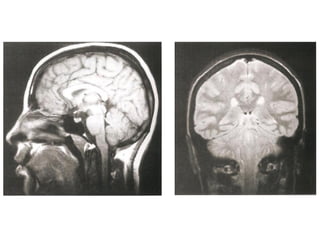

Ressonância Magnética do Crânio

• Sistema de obtenção de

imagens é mais sensível à

natureza molecular dos tecidos;

• Alta densidade tissular não

resulta em resolução de

contraste.

   Doenças da substância branca;

   Neoplasias;

   Doenças infecciosas;

   Distúrbios hemorrágicos;

   Distúrbios isquêmicos.

Tálamo

Hipotálamo

Hipófise

4º ventrículo